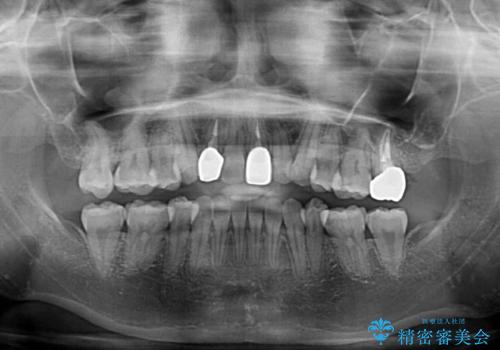

- 奥歯が痛いとのことで来院された患者様です。

上顎親知らず周辺の炎症と、神経組織の失活した歯の炎症による痛みが認められたため、親知らずの抜歯と根管治療を行いました。

根管治療を行った歯はクラウンによる補綴治療が必要となりますが、高校生の頃に行った矯正治療の後戻りも気になるとのことで、補綴治療を行う前に矯正治療を行うこととしました。

後戻りは軽度であり、インビザラインにて歯列を整え、その後にオールセラミッククラウンにて補綴治療を行うこととしました。